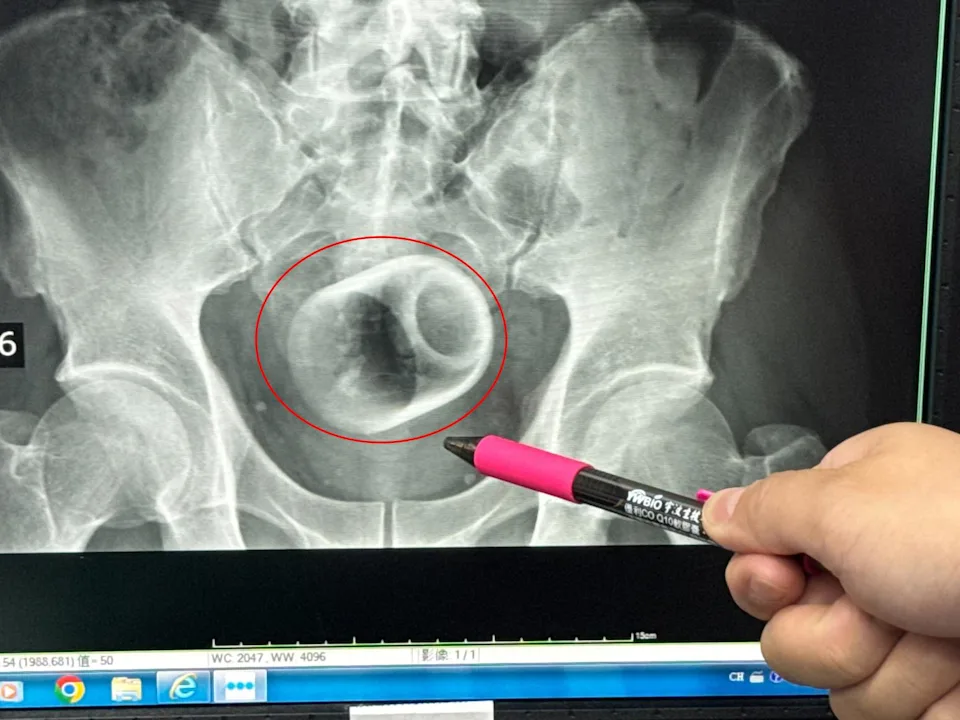

Discovered the ceramic cup during X-ray scan

It wasn’t until an X-ray scan was performed that the medical team discovered a 6cm-wide, 8cm-tall ceramic cup inside the pelvic area, with its opening facing downward.